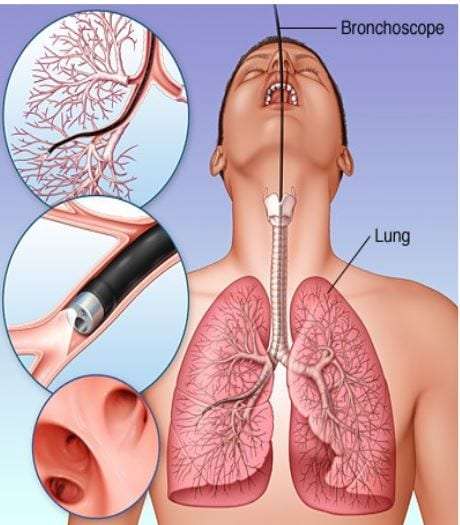

Фотографии и информация о бронхоскопии при туберкулезе